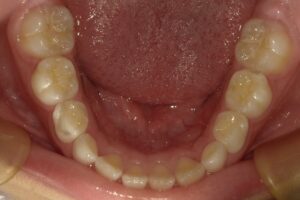

プレオルソを装着したところです。

歯列が綺麗になりました。